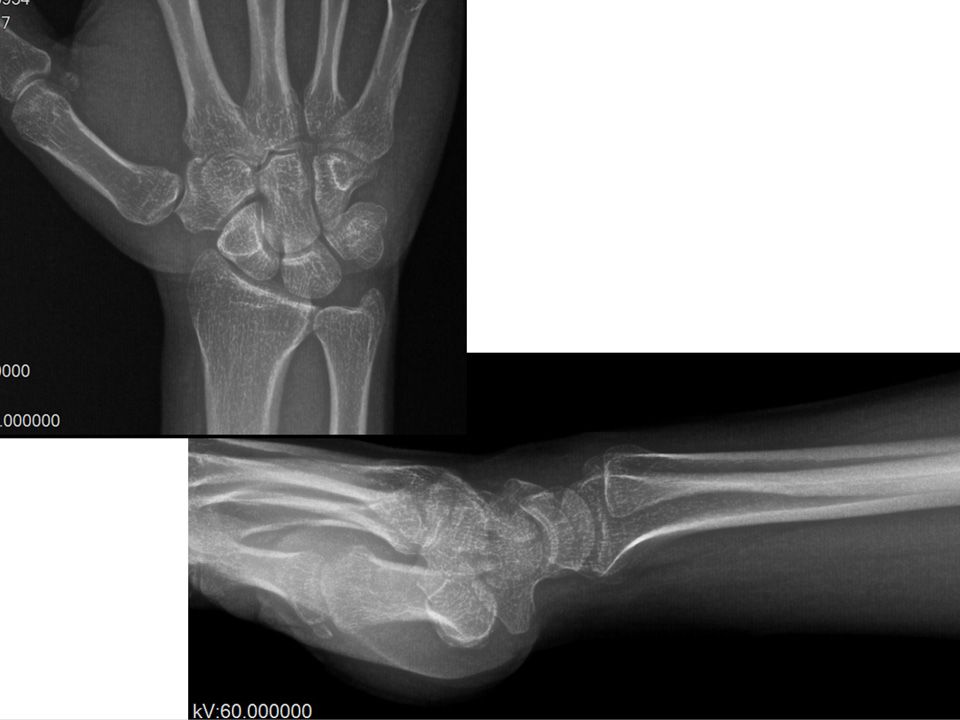

37 yaş, erkek, mobilyacı, sağ el dominant2-3 yıldır mevcut olan sol el bileği ağrısıLunat dorsalinde hassasiyetEl bilek fleksiyonu 50*, ekstansiyonu 50* ve ağrısız